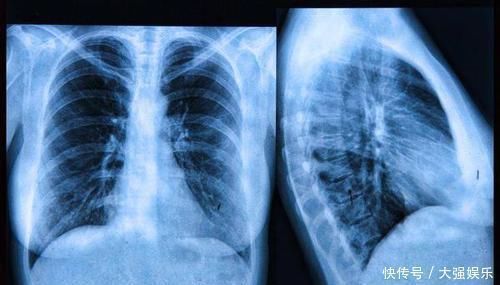

目前我国最为高发的癌症类型就是“肺癌”,每年新发的肺癌患者达到了近80万。但肺癌的整体治愈率却并不高,有近80%的患者在发现肺癌时,就已经到了中晚期阶段!

这是因为“肺”属于呼吸器官,它也是人体内为数不多缺乏末梢神经的器官!

所以,当肺部发生癌变之后,早期往往没有疼痛感觉。随着病情发展,患者多会出现咳嗽、痰中带血、咯血等症状表现。除此外,肺癌还有一个不典型症状:肩背部疼痛!

【 癌症|上半身一个表现,可能暗示肺部发生癌变,4类人最好早做CT排查】除了以上四类人群之外,即便是不符合高危的人群,从40岁左右也应定期进行肺部健康筛查。目前最有效监测肺部健康与否的方式,就是低剂量螺旋CT,这种检查手段的分辨率较高,可发现肺内微小病变,对肺癌初步筛查有重要意义。